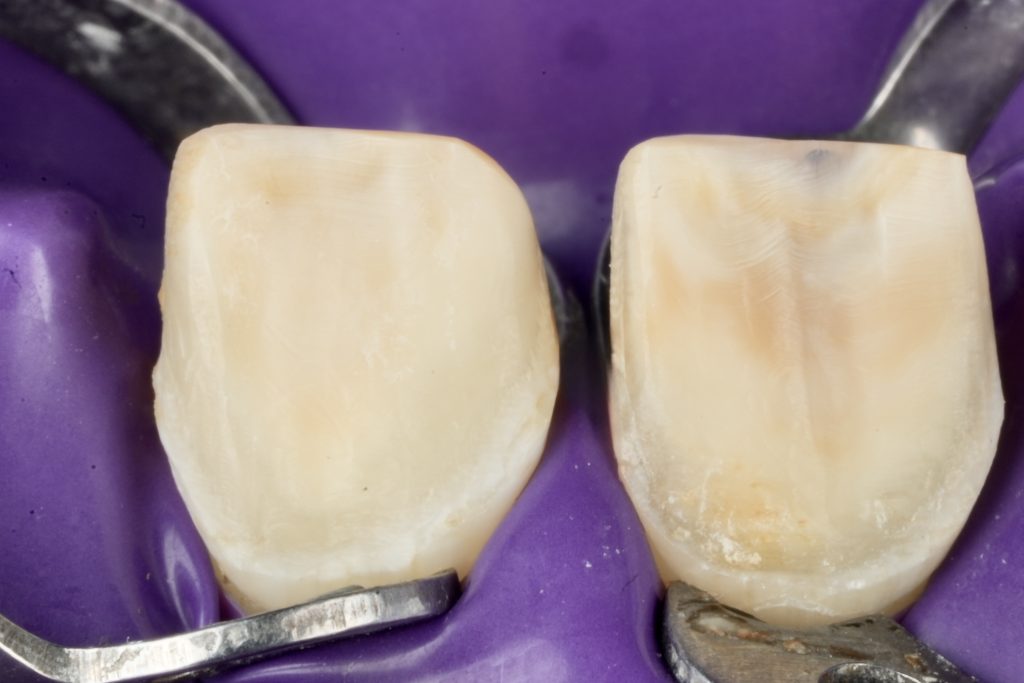

Each veneer was etched with 9 % HF acid for 20 seconds, silanated, and dried. Teeth were treated with 37 % phosphoric acid and universal adhesive (Clearfil Universal Bond Quick). Light-cure resin cement (Variolink Esthetic LC) was applied under full-arch rubber-dam isolation. Excess cement was removed and polymerization performed for 40 s per surface (Fig 4).